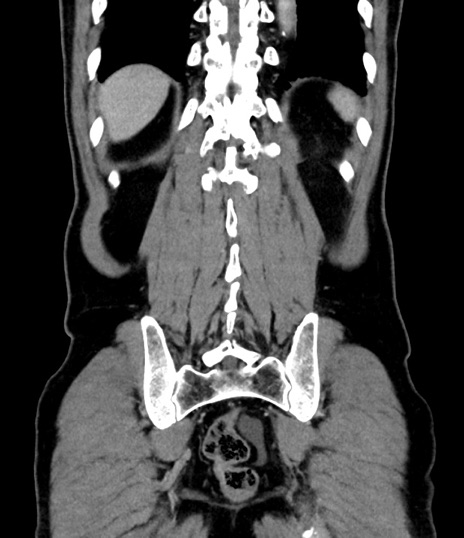

横断像

【症例】 60歳代男性

【主訴】 黒色吐物

【現病歴】 4日前から嘔気自覚、2日前の朝食後にも嘔気あり、自分で手で嘔吐反射起こし嘔吐したところ血が混ざっていたため受診。

【既往歴】 5年前汎発性腹膜炎を伴う急性虫垂炎で手術、高血圧、前立腺肥大症、高脂血症

【身体所見】 腹部正中に手術癩痕あり 腹部平坦・軟圧痛なし膨満感あり

【データ】WBC 8400、CRP 4.54